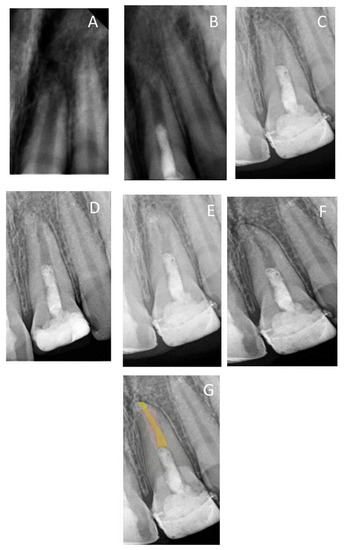

| 1 | Male | 9 | 11 | Trauma | 11.088 | 0.405 | 0.63 | 2 years | No lesion | NA |

| 2 | Male | 9 | 21 | Trauma | 10.48 | 0.477 | 1.021 | 3 years | 6 | No respond |

| 3 | Male | 9 | 11 | Trauma | 12.562 | 0.584 | 1.53 | 3 years | 6 | Respond |

| 4 | Male | 9 | 21 | Trauma | 12.36 | 0.44 | 1.1 | 3 years | 6 | Respond |

| 5 | Male | 10 | 11 | Trauma | 14.014 | 0.81 | 0.92 | 3 years | 6 | No respond |

| 6 | Male | 11 | 21 | Trauma | 14.38 | 0.78 | 0.9 | 2 years | 6 | NA |

| 7 | Female | 8 | 21 | Trauma | 10.01 | 0.36 | 1.02 | 3 years | 6 | No respond |

| 8 | Female | 8 | 47 | Caries | 10.51 | 0.41 | 1.28 | 2 years | 9 | NA |

| Preoperative | 10.36 | 1.14 | 0.48 |

| 6th Month | 10.47 | 1.15 | 0.72 |

| 12th Month | 10.64 | 1.28 | 0.74 |

| 2nd Year | 10.79 | 1.29 | 0.76 |

| 3rd Year | 10.92 | 0.65 | 0.86 |

| 8th Year | 11.4 | 0.24 | 0.98 |